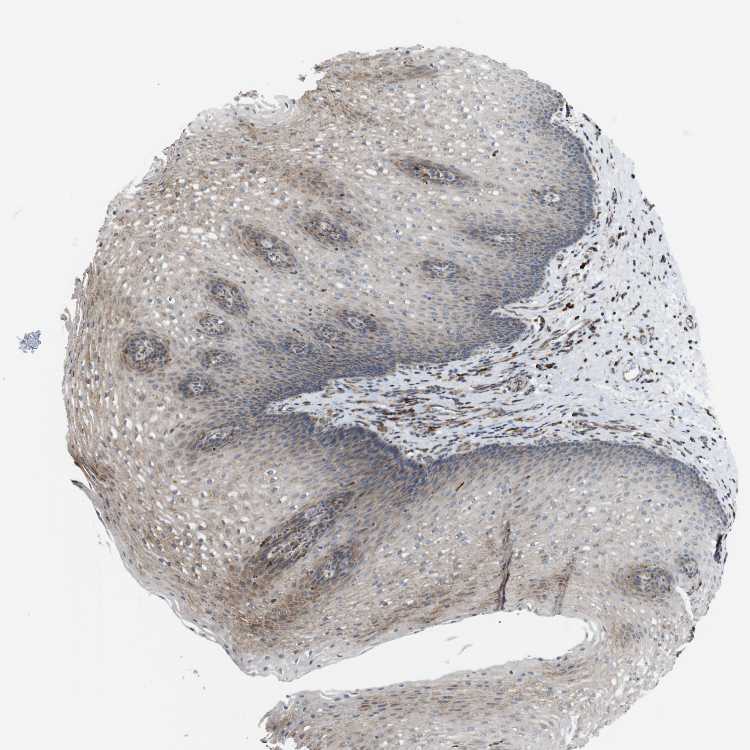

ESOPHAGUS - Antibody stainingi

Antibody staining in the annotated cell types in the current human tissue is reported as not detected, low, medium, or high, based on conventional immunohistochemistry profiling in selected tissues. This score is based on the combination of the staining intensity and fraction of stained cells.

Each image is clickable and will lead to virtual microscopy that enables deeper exploration of all samples and also displays staining intensity scores, fraction scores and subcellular localization as well as patient and tissue information for each sample.

Antibody HPA012761Antibody HPA015127

Squamous epithelial cells LowNot detected